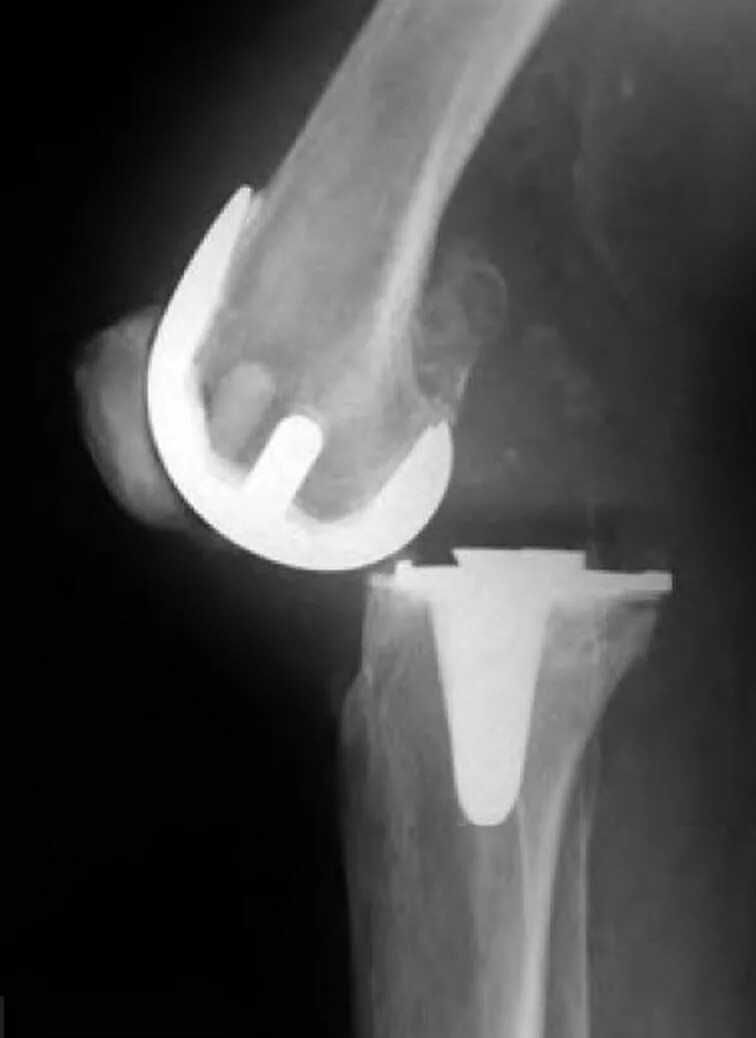

Вывих после эндопротезирования тазобедренного